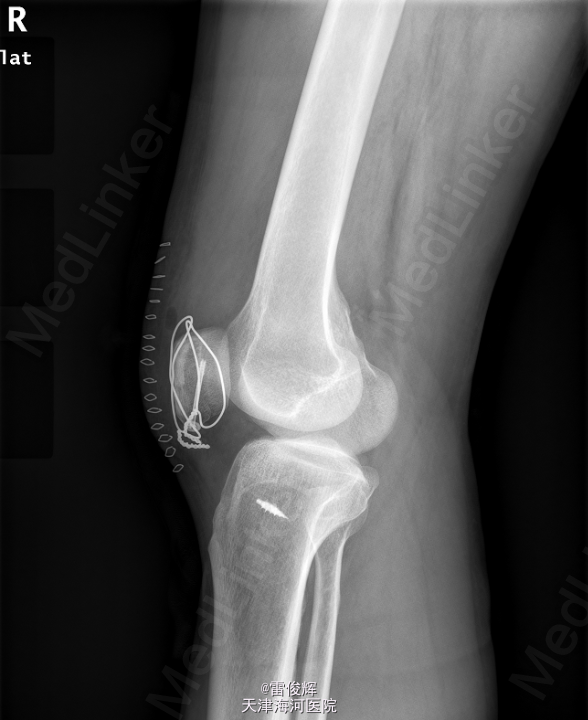

初步诊断: 右髌骨骨折 患者入院后完善检查,排除禁忌,全麻下行右髌骨骨折切开复位内固定+髌韧带修补术。

术后予抗炎止痛护胃补液等对症支持治疗.创口清洁,干燥,无感染征象,肢端活动感觉可,术后X片提示骨折复位固定满意.